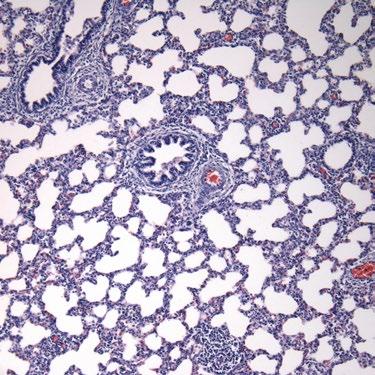

Microscópicamente, se observa neumonía intersticial (Figura 4), miocarditis (Figura 5), miositis en varios músculos esqueléticos (Figura 6), encefalitis e inflamación perivascular, a veces asociada con vasculitis multisistémica (Figura 7).

Las células inflamatorias implicadas son macrófagos, linfocitos y plasmocitos.

Es importante destacar que estas lesiones varían de discretas a acentuadas, por lo que es necesaria una evaluación minuciosa de todos los tejidos.

Estas lesiones microscópicas se observan en fetos abortados por PCV3 y en lechones recién nacidos y destetados.

Figura 4: Lechón positivo para PCV3. Microscopía de tejido pulmonar con infiltrado inflamatorio intersticial de macrófagos, linfocitos y plasmocitos multifocal discreto, además de infiltrado perivascular de macrófagos y linfocitos multifocal moderado. HE, 20X. Fuente: Molossi, 2021.